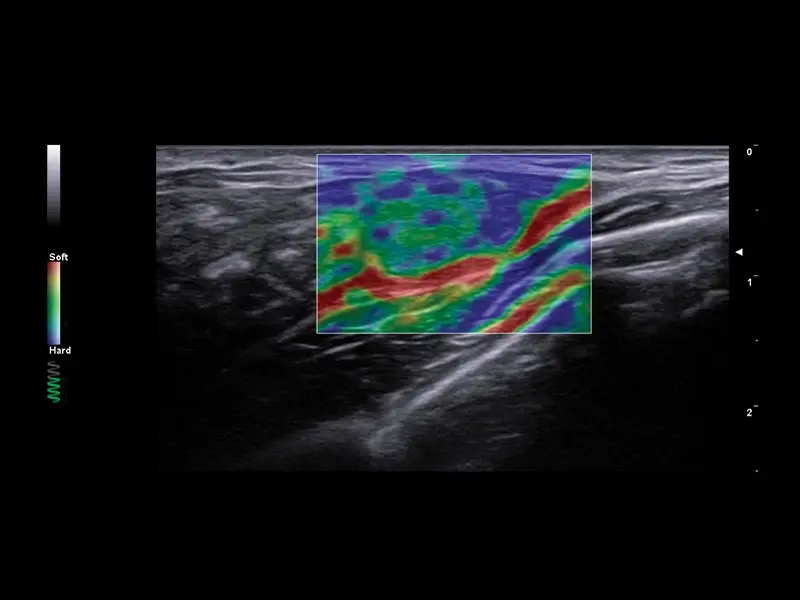

S MyLab™ A50 získáváte možnost provádět široké spektrum vyšetření, včetně jater, srdce, gynekologie a porodnictví, cév, prsu, štítné žlázy, muskuloskeletálního systému, urologie a pediatrie.